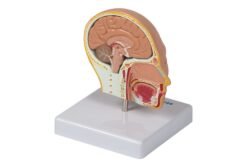

Modelo anatómico del cabeza